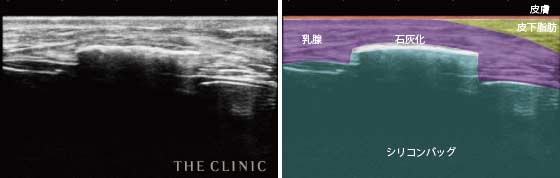

乳腺や脂肪、筋肉などの層の状態をみることができるので、シリコンバッグのまわりにある皮膜の厚さや石灰化の状態だけではなく、シリコンバッグが挿入されている正確な位置やシリコンバッグの破損なども確認することができます。

- 石灰化

- シリコンバッグの周りに石灰化が起きている